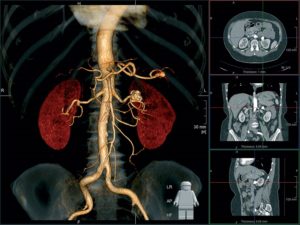

- МРТ соединяет свойства электромагнитного поля. Оно передает информацию в виде высокочастотных импульсов, которые компьютер считывает в виде четких срезов толщиной не более 1–2 мм. Последние модели сканеров формируют трехмерное изображение почки с прилегающими кровеносными сосудами, что необходимо при сложных операциях, трансплантации.

- трехмерное построение почки и реконструкция опухоли;

КТ и МРТ почек — это высокоточные визуализационные методы исследования. КТ почек — это рентгенологический метод исследования, методика которого базируется на возможности объемной визуализации тканей и проектировании данных на экран компьютера. КТ почек бывает без использования контраста и с использованием йодсодержащего контраста для лучшей визуализации сосудов и тканей.

Суть обоих методов заключается в послойном сканировании организма. В результате чего получаются томограммы (отсюда название методик).

После чего они обрабатываются компьютером, который формирует из них 3D-модель того или иного участка организма.

- При проведении магнитно-резонансной томографии применяются свойства магнитного поля и радиочастотных импульсов. При этом получаются 3D изображения исследуемого органа, которые показывают наличие патологии и ее локализацию.

- Компьютерная томография проводится благодаря сочетанию принципа диагностики лучевого типа (рентгеновское излучение) с современными компьютерными технологиями. В результате получают послойное изображение органа во множестве срезов.